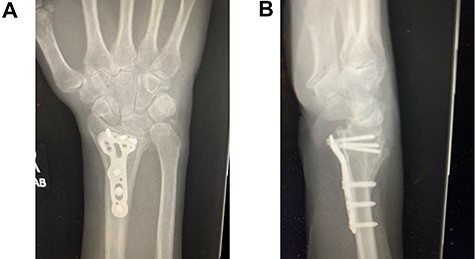

A 52-year-old female patient presented following failed fixation of a left distal radius fracture. She had undergone surgical fixation of a distal radius fracture 8 years previously and now complained of persistent and continuous pain, restricted range of movement and functional limitation. Her imaging confirmed a healed distal radius fracture in neutral alignment but with evidence of degenerative change in the radiocarpal joint and migration of the metalwork so that the distal screws penetrated the wrist joint (Fig. 1A and B).

(A and B) PA and lateral radiographs showing failed distal radius fixation with radiocarpal degenerative change.